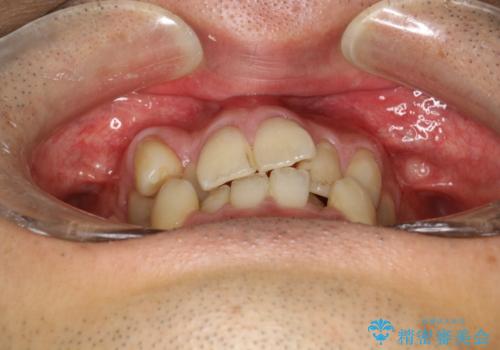

ガタガタの歯並び、八重歯をなおしたい、骨格性下顎前突 カモフラージュ矯正

- 前歯のガタガタと八重歯を治したいということで矯正を希望された患者様です。

骨格的に上顎骨が小さいために相対的に下顎骨が前に出ていたため、歯の傾きなど理想的な仕上がりが難しく、外科矯正ではなく歯列矯正の場合はカモフラージュ矯正になること説明の上、矯正治療を進めることになりました。